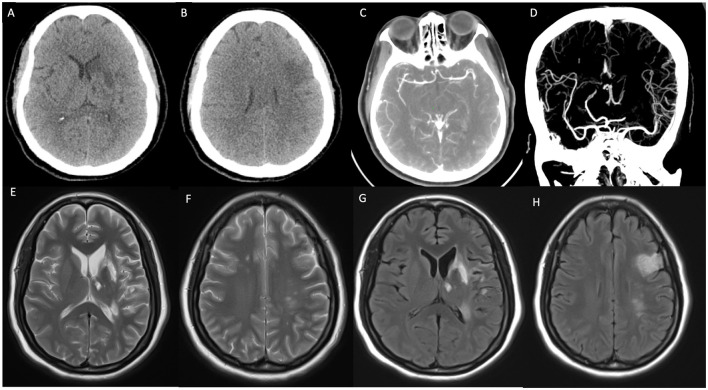

心房黏液瘤是一种罕见的良性肿瘤,可引起多种并发症,包括脑梗死。我们提出一个病例52岁的女性患者谁发展脑梗死引起的心房粘液瘤。患者成功手术切除了肿瘤,并对梗死进行了相应的治疗。然而,术后15个月,患者出现了新的神经系统症状。影像学检查显示多发性脑转移,与肿瘤细胞播散的可能性一致。这种罕见的并发症强调了心房黏液瘤切除术后长期监测的重要性。脑转移的发生虽然罕见,但应在随访中予以考虑,特别是在发生心房黏液瘤相关栓塞事件的患者中。我们的病例强调了即使在最初成功的手术干预后,脑黏液瘤转移的可能性,强调了对此类患者进行全面随访和警惕监测的必要性。

Atrial myxoma is a rare benign tumor that can cause a variety of complications, including cerebral infarction. We present a case of a 52-year-old female patient who developed cerebral infarction caused by an atrial myxoma. The patient underwent successful surgical resection of the tumor, and the infarction was managed accordingly. However, 15-months post-surgery, the patient developed new neurological symptoms. Imaging studies revealed multiple cerebral metastases, consistent with the possibility of seeding of tumor cells. This rare complication emphasizes the importance of long-term monitoring after the resection of atrial myxomas. The occurrence of metastasis in the brain, though rare, should be considered in follow-up care, particularly in patients who have had embolic events related to atrial myxomas. Our case highlights the potential for cerebral myxoma metastasis even after initial successful surgical intervention, underscoring the need for comprehensive follow-up and vigilant monitoring of such patients.